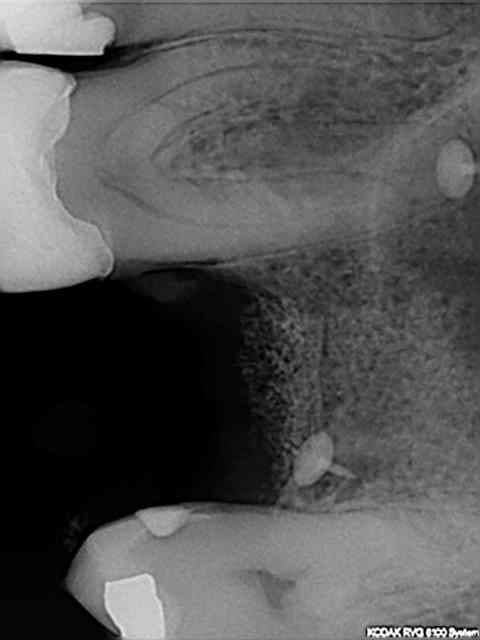

autres coupes...

3f3boxni50k58rq7e9ce9ddqrxgk - Eugenol

11-12: RX avant-après